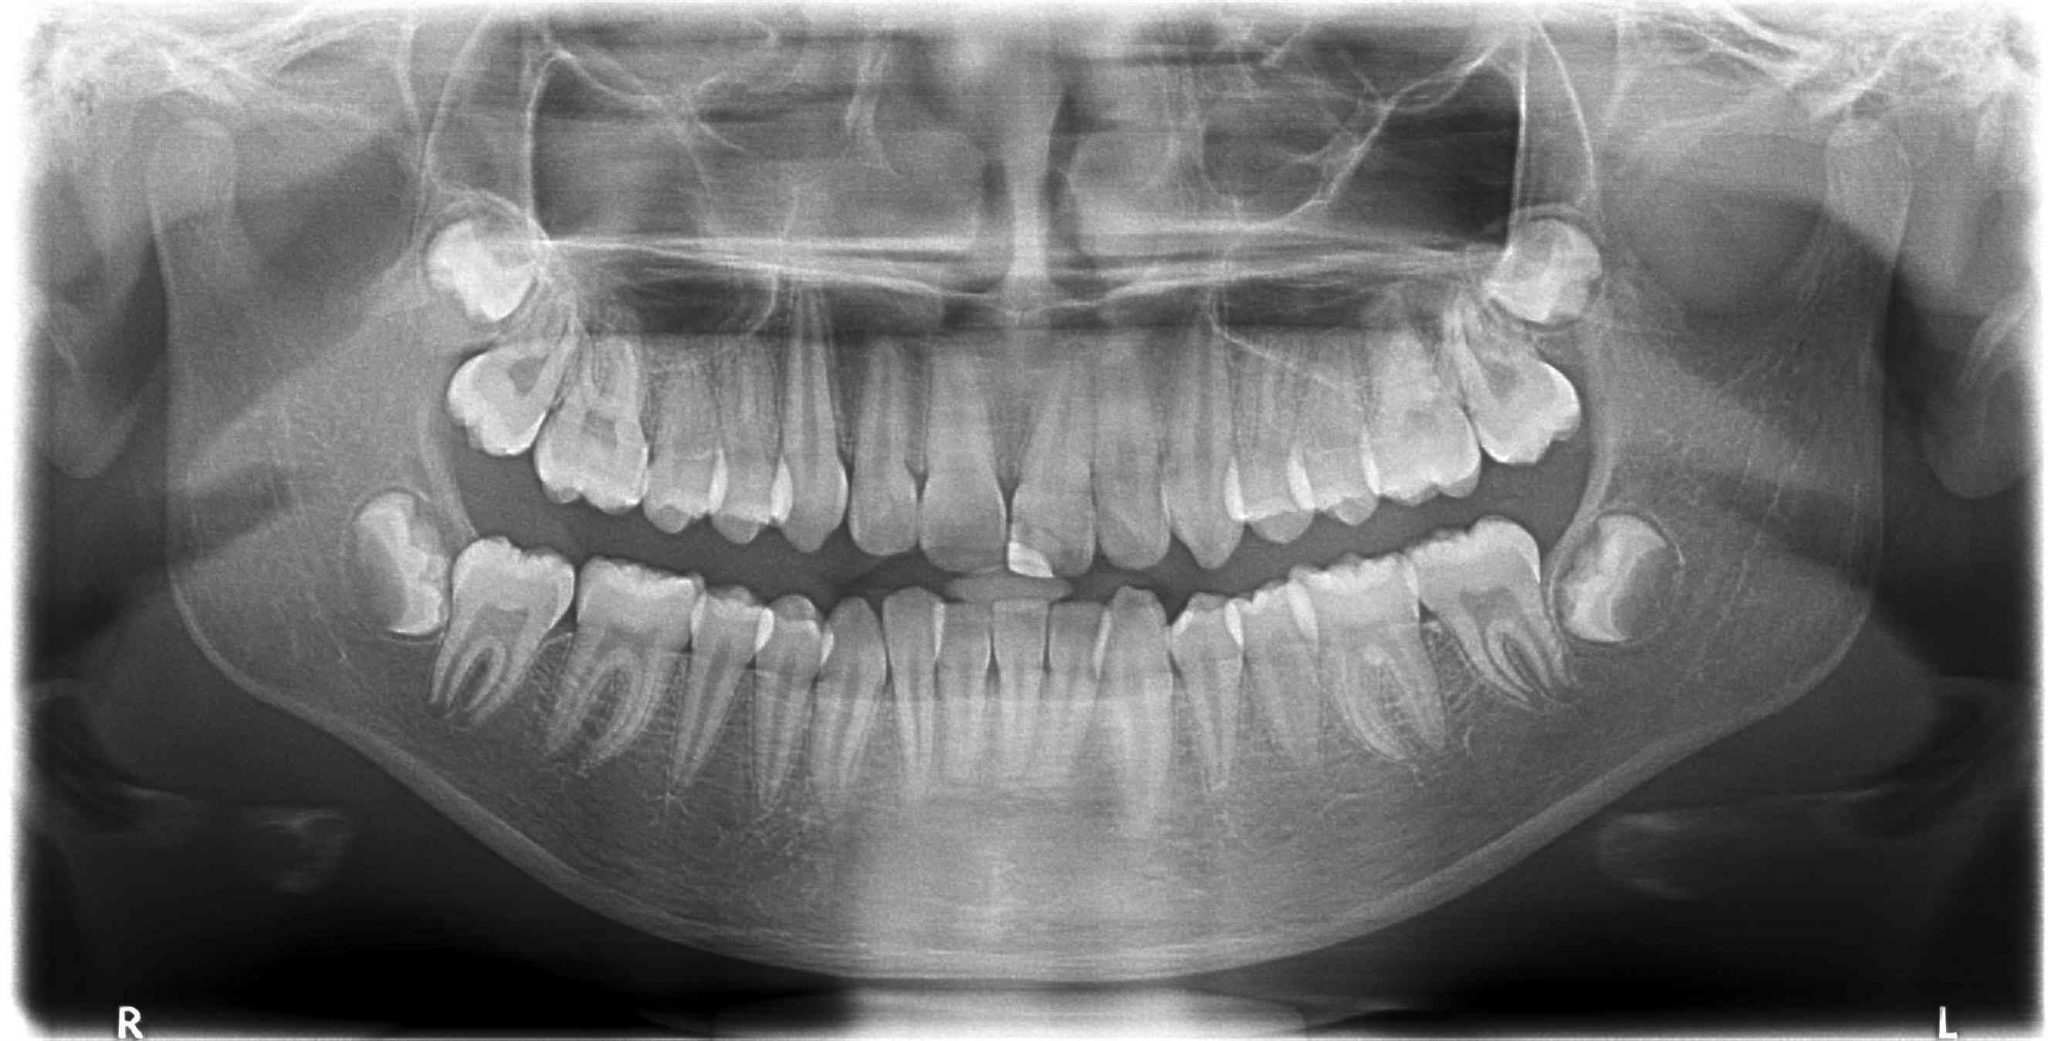

Restore your smile with a durable dental implant crown. Learn how this restorative procedure replaces missing teeth, ensuring a natural look and optimal oral function. Discover the benefits of high-quality dental prosthetics, the installation process, and essential long-term care tips to maintain your implant-supported crown for a healthy, confident, and long-lasting smile.